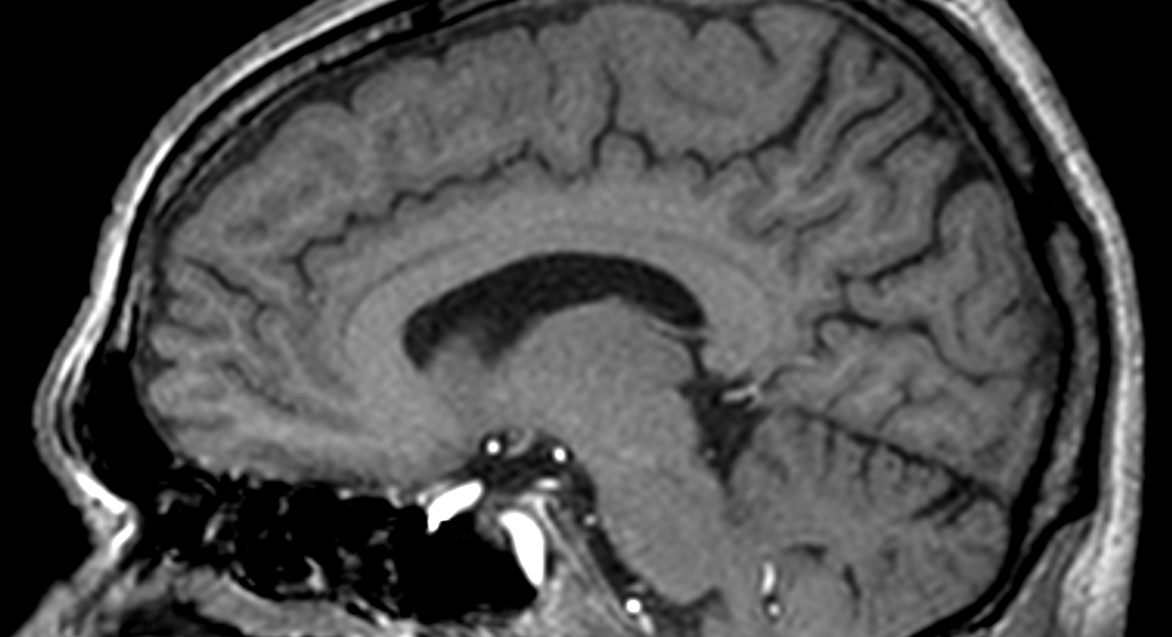

3D T1w TFE (sagittal reformat)

Sagittal 23Na bFFE